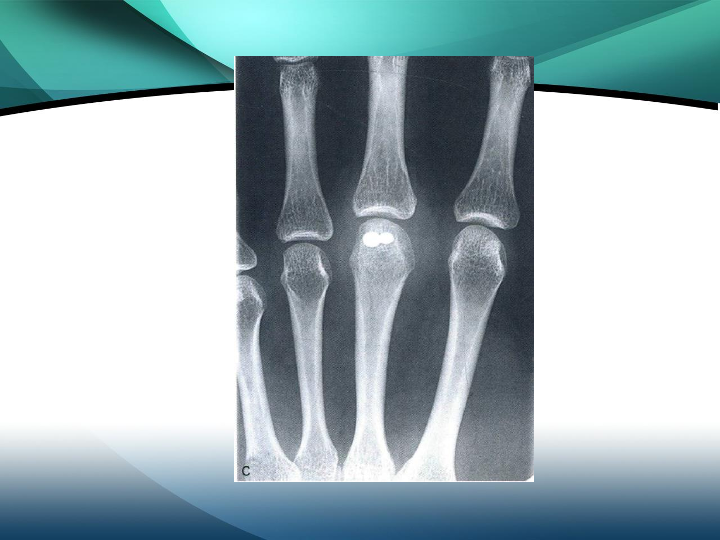

掌骨骨折